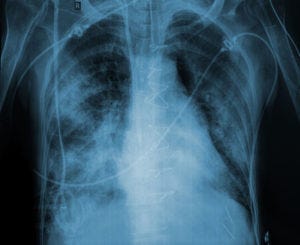

In acute respiratory distress syndrome (ARDS), using pleural pressure to adjust positive end-expiratory pressure (PEEP) has long been considered a cumbersome but theoretically ideal technique to optimize ventilator management. Using esophageal pressure as a surrogate for pleural pressure can allow one to calculate and minimize the transpulmonary pressure gradient, elevations in which are the putative cause of ventilator-induced lung injury. But in a new randomized trial dubbed EPVent-2, titrating PEEP according to the esophageal pressure provided no clear benefits over empirical adjustment tending toward relatively high PEEP. The results were published in JAMA. Two hundred patients at 14 centers with moderate-to-severe ARDS were randomly assigned to either esophageal pressure-guided PEEP titration, or empirical high-PEEP strategy. (How high? They used tables from trials testing high-frequency oscillatory ventilation, e.g., 18 cm H2O of PEEP at FiO2 0.4 - 0.5, and 20 of PEEP for FiO2 0.5 - 0.8.) All patients could get neuromuscular blockade, sedation, and volume resuscitation according to their treating physicians. Prone positioning was only used as salvage therapy (the Proseva trial had not yet been published when this trial was designed). In practice, patients in both groups received very similar doses of PEEP for any given FiO2. There was no difference in groups in the primary outcome, a ranked composite score including death and ventilator-free days, nor in secondary outcomes such as 28-day mortality, ICU length of stay, etc. However, significantly fewer patients receiving esophageal pressure-guided PEEP required rescue therapy (4 vs 12). Barotrauma occurred in equivalent numbers of patients (5 vs 6). The results stand in contrast to a prior study (EPVent) which did show improved oxygenation and a trend toward improved survival with an esophageal pressure-guided PEEP strategy.